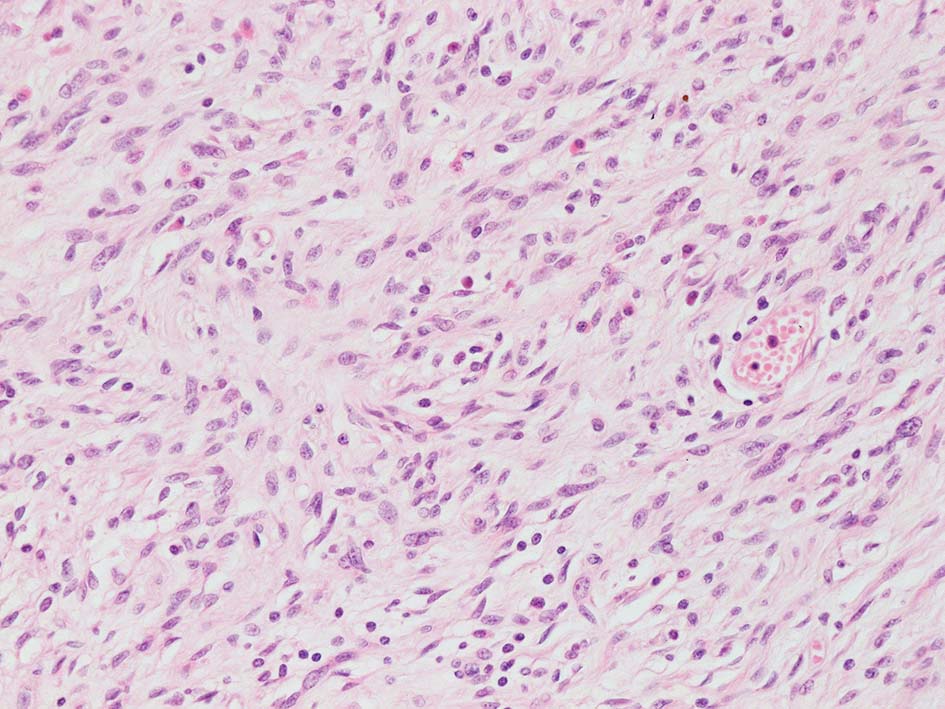

紡錘形異型メラノサイトが著明な間質反応(desmoplasia)を伴い増殖する特殊な色素性病変。*1. desmoplastic neurotropic melanomaは, desmoplastic melanomaのうち神経向性(neurotropism:神経周囲侵襲像)がめだつものでReedら*2が最初に報告した。

いずれも腫瘍細胞の異型性が乏しく, 背景の間質反応がめだつこと, メラニンの存在が目立たないことが特徴である。

“このため両者を臨床的にも病理学的にも色素性病変と診断することが困難”であり, 初回生検時には瘢痕病変や皮膚線維腫などと誤認されることが多い。

再発腫瘤病変の組織像